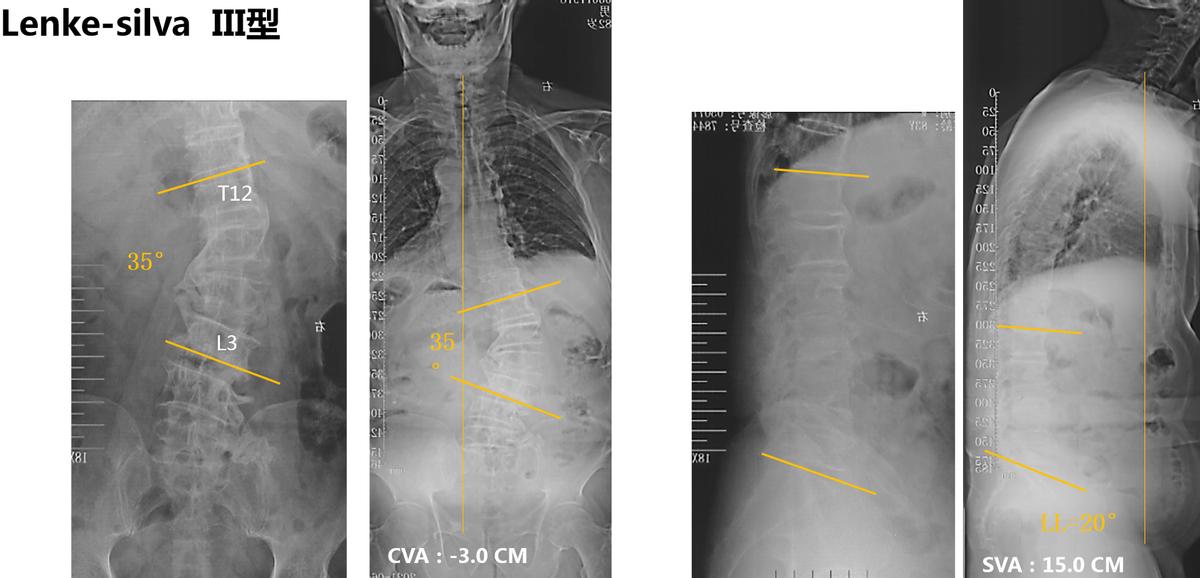

从患者的X线片可见,腰椎 35度右侧凸,顶椎L1/2。冠状位整体平衡还可以。矢状位:SVA 15.0CM。LL 20°。患者主诉病情加重前,无身体前倾等失平衡表现,腰痛引起异常体位。因此,我们判断患者的脊柱侧弯属于 Lenke-silvia III型 ADS。

术前影像学资料:

X线片